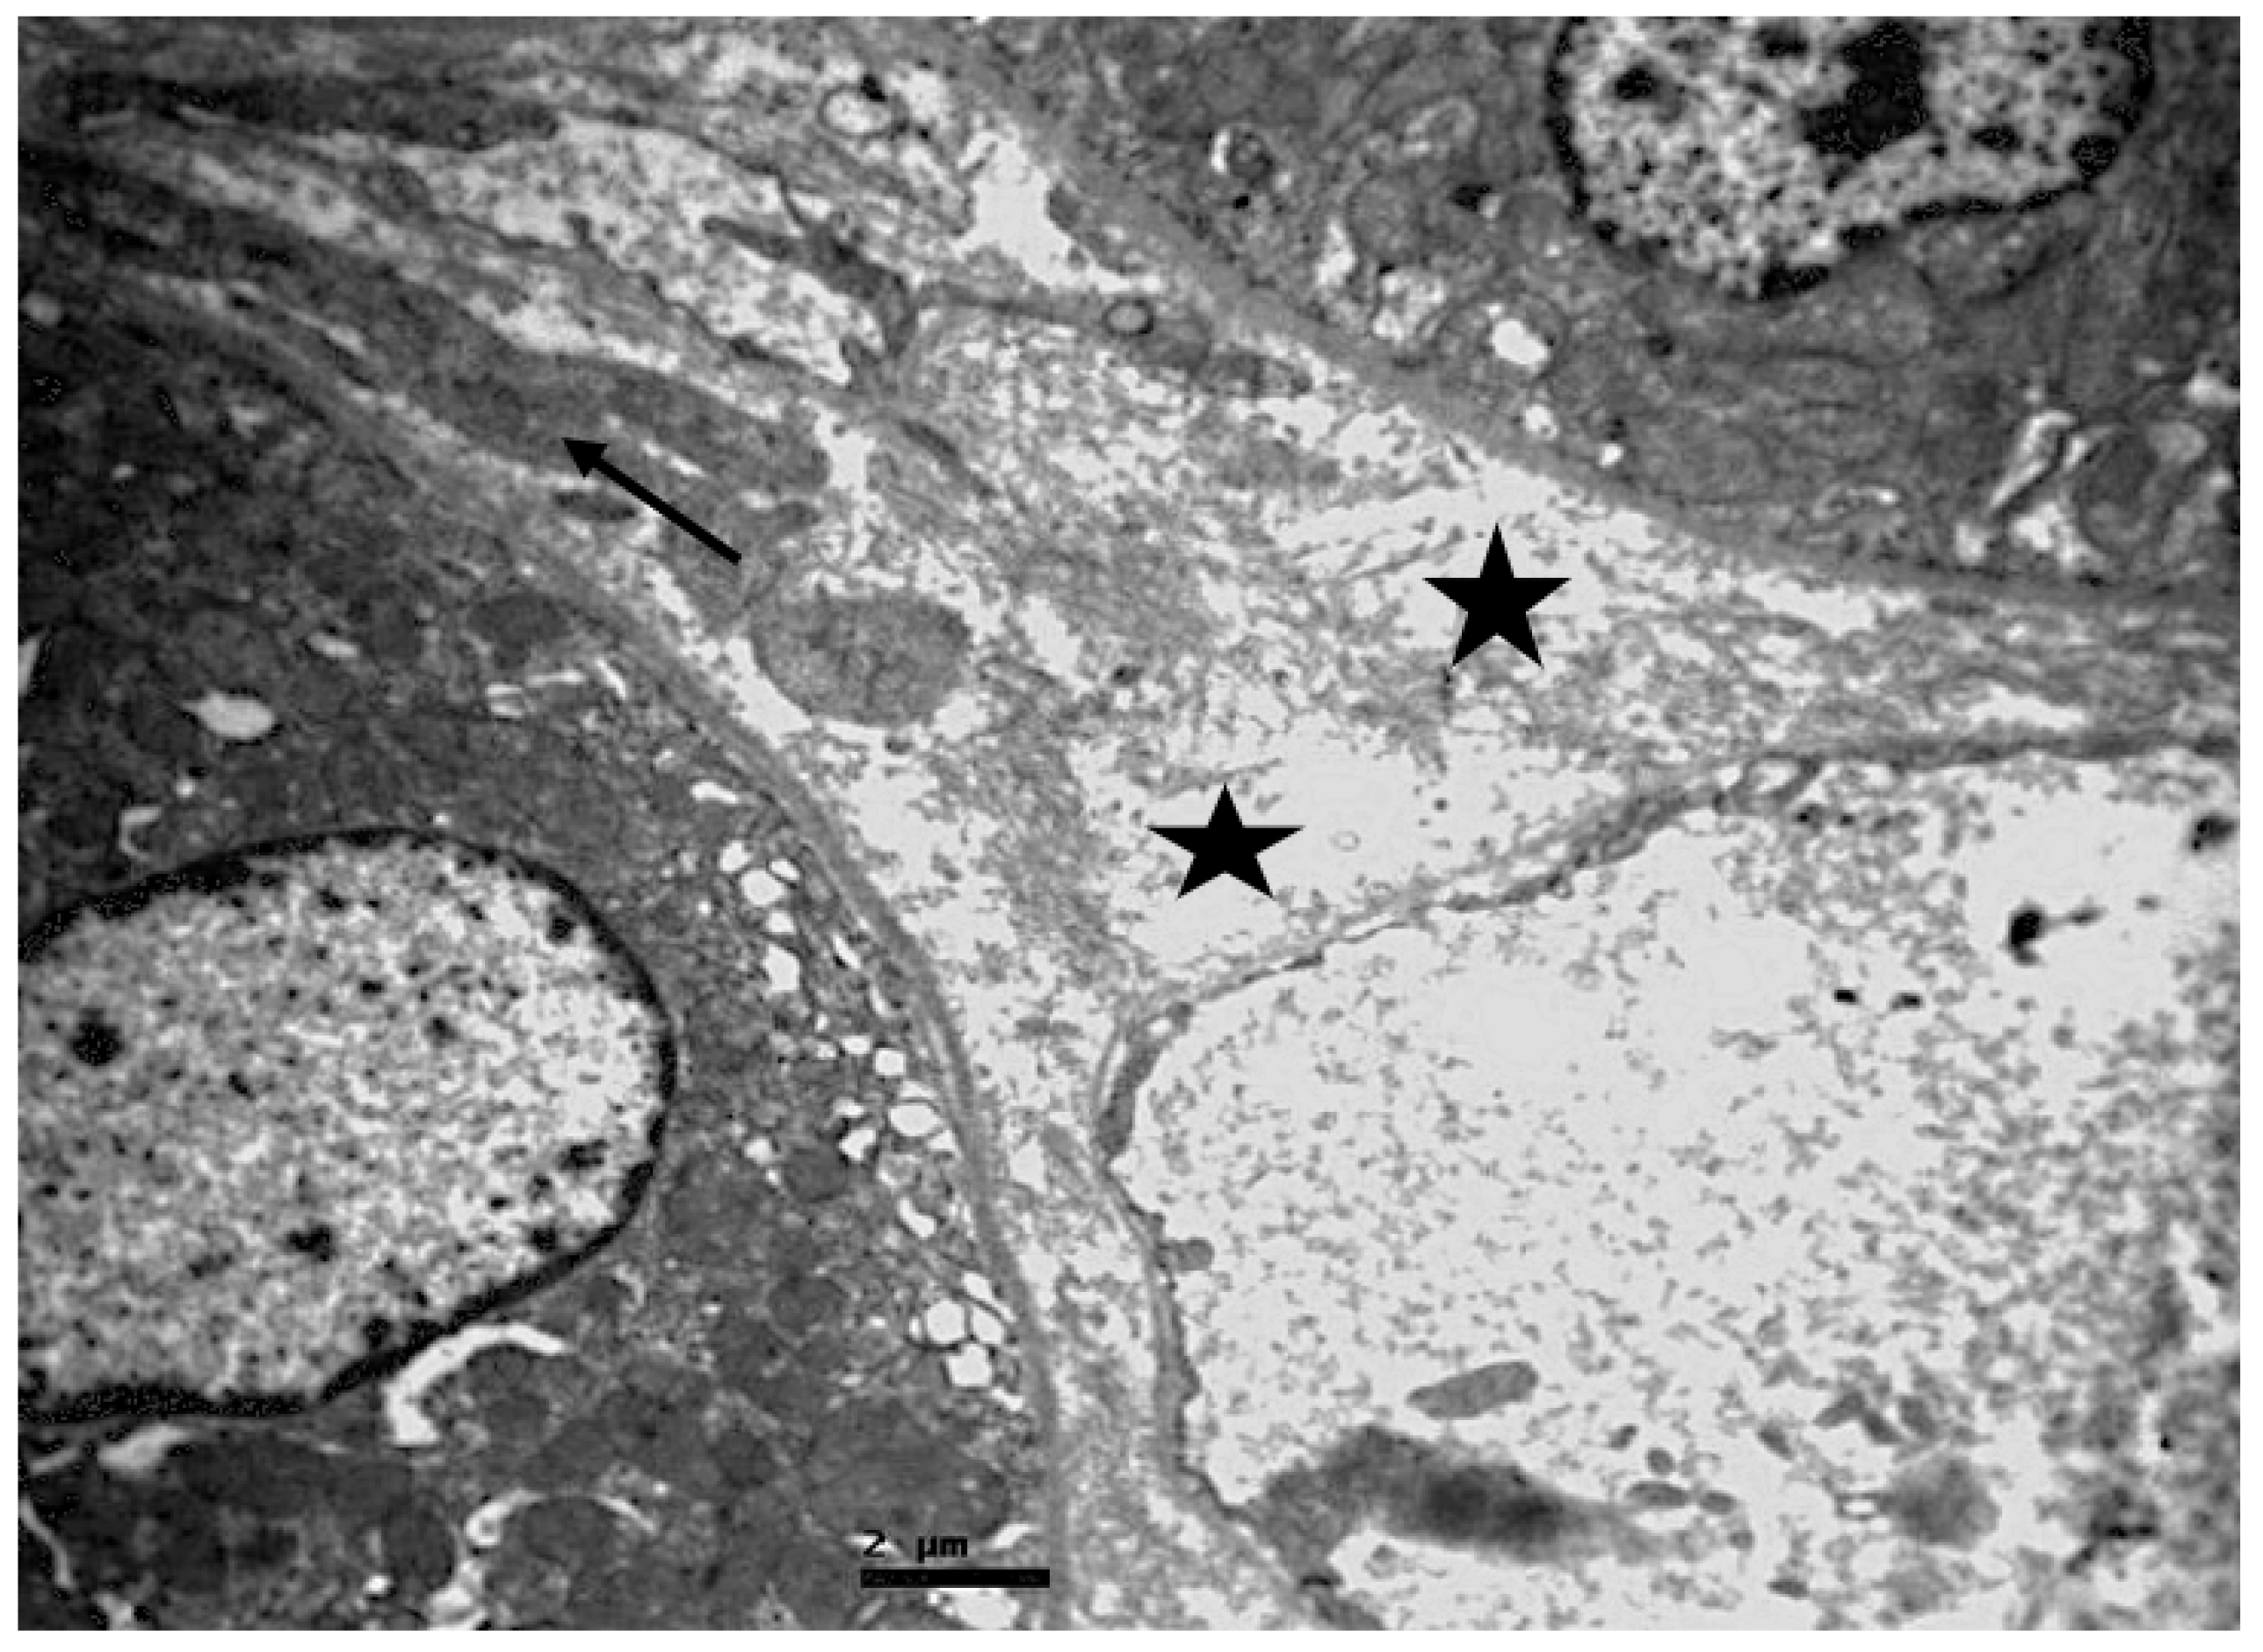

2.2. Electron Microscopic Evaluation